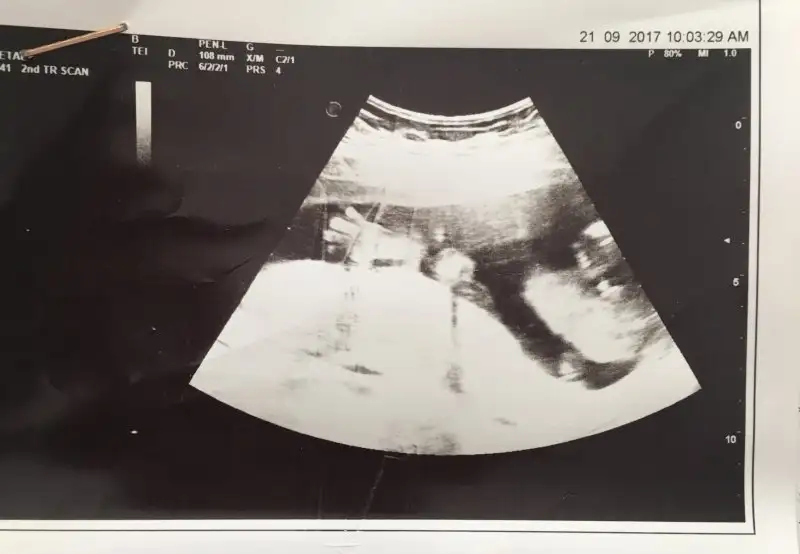

Mşlh ne güzel bir an yakalamış doktor